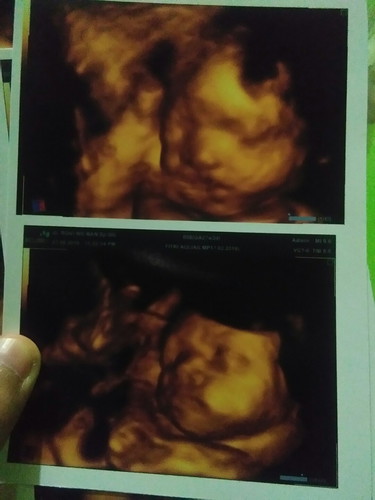

usg 28 weeks

Alhamdulillah perkembangan dan kehamilan ibu semua normal ya nak.. Udh gk sabar nunggu 2 bln lagi ktmu kamu nak q.. ??